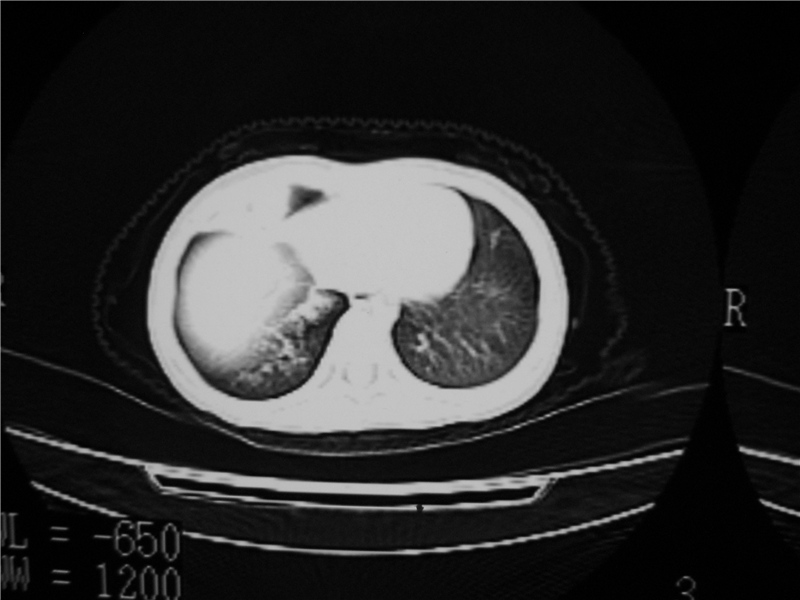

右肺中叶及下叶内段大片实变密度增高影,可见支气管气象,肺炎.

摄吸气及呼气相对比片,本例为有肺中叶阻塞性炎症、不张,右肺下叶阻塞性炎症。

1)右肺炎症并右肺中叶肺不张,右肺上叶充气不良。2)右侧支气管异物不排除。

结合临床考虑支气管异物并阻塞性肺炎、肺不张。